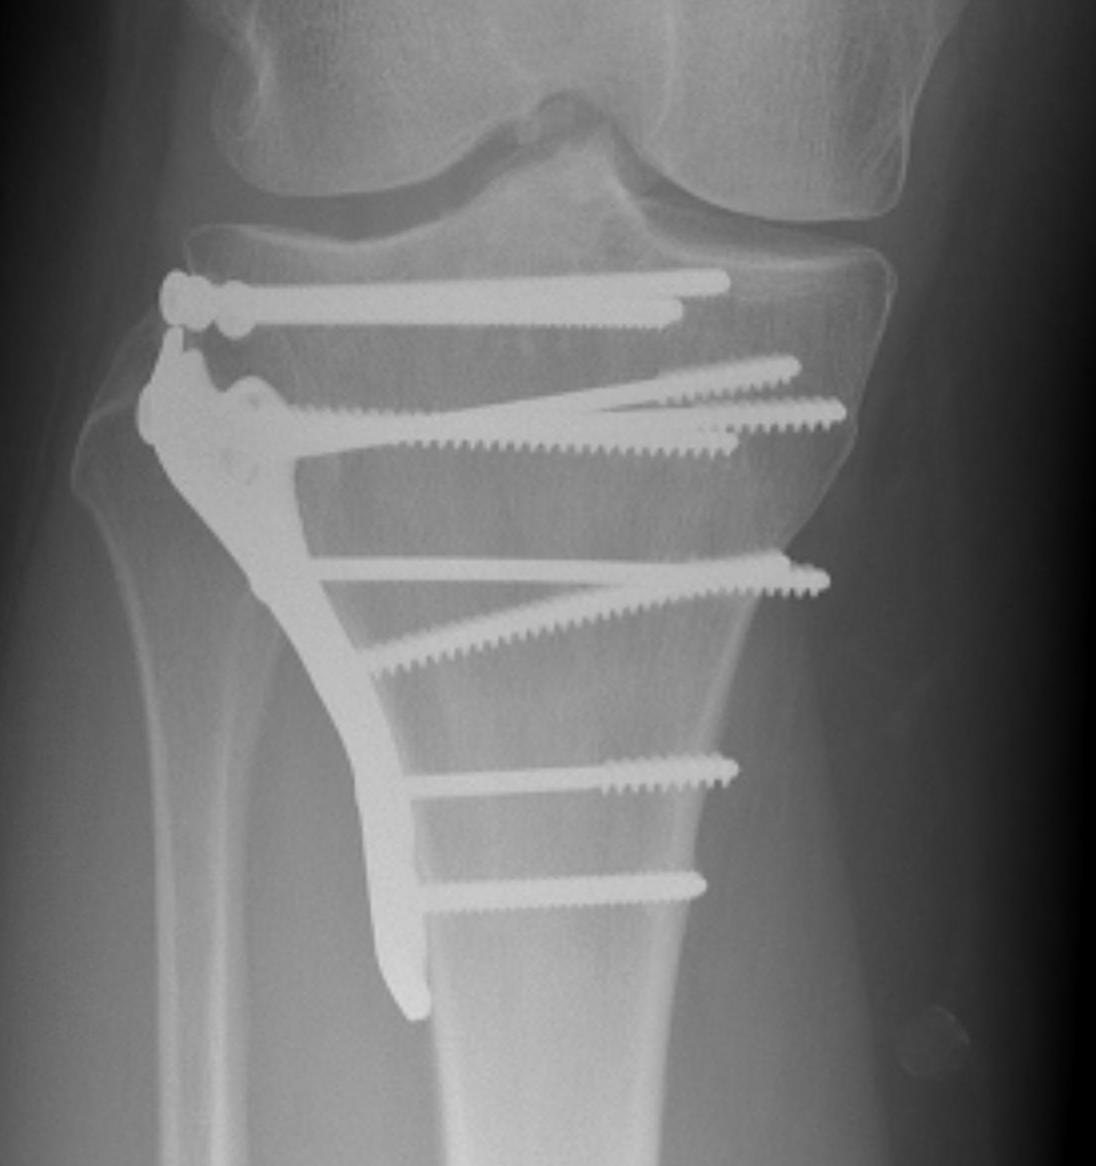

Buttress plate / Antiglide Plate

- physically protect underlying thin cortex

- often used with metaphyseal fixation

- buttress is intra-articular (tibial plateau)

- antiglide is metaphyseal - diaphyseal